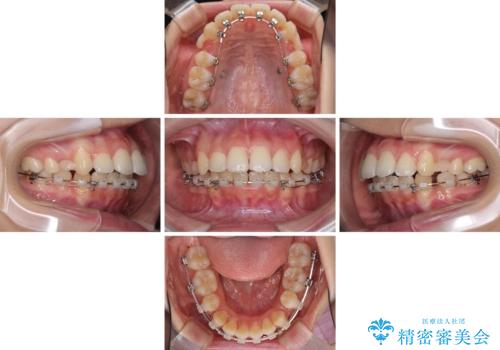

- 矯正装置

- ハーフリンガル

- 口元の突出感を気にして来院された患者様です。

上下左右の第一小臼歯4本を抜歯して口元を下げる治療計画としました。

目立たない装置が希望であったため、上顎が裏側装置である、ハーフリンガル装置を選択されました。

3年半ほどで終わる予定でしたが、途中引っ越し、出産、引っ越し、出産を繰り返し、なかなか来院することができず、装置を外すまでに8年以上の期間がかかってしまいました。